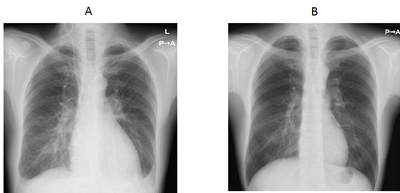

Figure 1A shows a chest X-ray image of a patient who was admitted to the hospital because of shortness of breath due to heart failure. The heart is enlarged and fluid exudes into the lung, which is seen as a white shadow. The echocardiogram in Figure 2A shows that the heart is enlarged and its motion is compromised. For such patients, several medications are administered to eliminate the burden on the heart. After a patient's condition stabilizes, an oral medication called a beta-blocker is added. Beta-blockers are one representative type of medication for heart failure. It acts by slowing down the heart rate to rest the heart. Since these actions may cause a relapse of fluid retention in the lung, a beta-blocker is started at a low dose and carefully increased over several weeks. If patients are being effectively treated with medication, their heart size is reduced (Figure 1B) and the force of heart contractions is improved (Figure 2B). The effectiveness of beta-blockers varies by patient; it is evaluated based on symptoms and examinations such as echocardiography and blood tests. The following echocardiograms were obtained from a patient for whom medications were effective. The effectiveness of medications for heart failure varies from person to person. Medications are not necessarily effective for all patients with heart failure. The type and dose of medications are adjusted for individual patients based on their blood pressure, heart rate, symptoms, echocardiography findings, and blood test results.